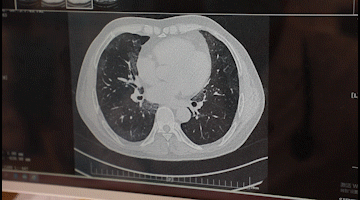

李先生入院后,胸科醫(yī)院吳昌歸院長、朱運奎副院長組織科室進行了深入討論,為其做了詳細檢查。醫(yī)生先做了導(dǎo)航下氣管鏡冰凍活檢,但病理未獲明確診斷。根據(jù)胸部CT特征、病變過程治療的反應(yīng),醫(yī)生懷疑是罕見的肺泡蛋白沉積癥。再經(jīng)肺泡灌洗液分析、PAS染色及診斷性分段灌洗后復(fù)查,證明醫(yī)生診斷正確。李先生確診為“肺泡蛋白沉積癥(繼發(fā)性)、肺炎、1型呼吸衰竭,并伴有慢性乙肝、高血脂癥等。

經(jīng)過4次的治療,李先生沉著于肺泡內(nèi)蛋白樣物質(zhì)漸漸消失,灌洗液為透明色。復(fù)查胸部CT肺部病變明顯吸收。經(jīng)再次灌洗治療后病變完全吸收,恢復(fù)健康。